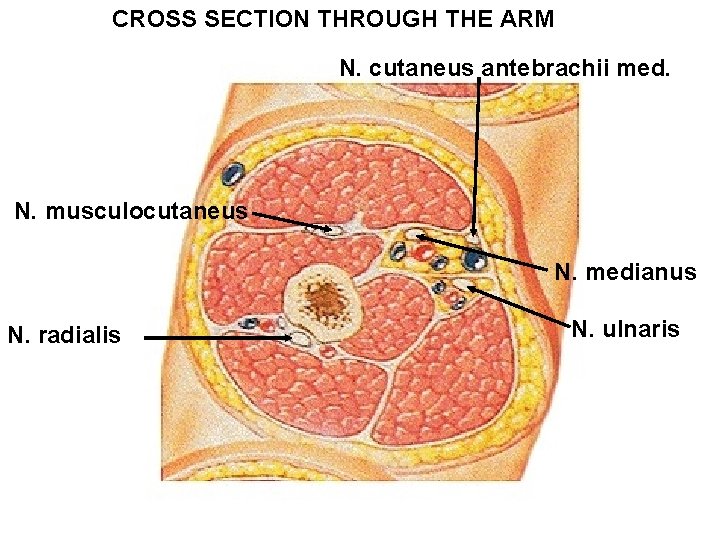

CROSS SECTION THROUGH THE ARM N. cutaneus antebrachii med. N. musculocutaneus N. medianus N. radialis N. ulnaris